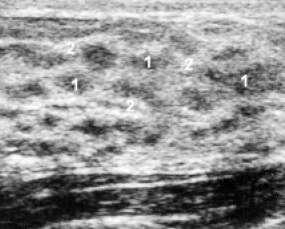

Мужчина 60 лет.В течении 2-3 нед отмечает увеличение,болезненность левой грудной железы.

Коллега, почему именно АФП и ХГЧ вы рекомендуете?Истинная гинекомастия левой грудной железы.Анализ крови на АФП,ХГЧ,консультация маммолога

Денис, у положилого мужчины лоцируется железистая ткань более 11 мм ,следовательно существует более 1 года,наличие у мужчин железистого слоя выявляется при повышенной выработке эстрогенов -опухоли печени ( АФП ) ,яичек (ХГЧ) ,раке простаты , это мининимум анализов ,а вообще нужно сдать кровь на эстрадиол,тестостерон, ЛГ, ФСГ,пролактин.Нельзя исключить и очаговые изменения,как заметил Алексей ,поэтому маммография.

Так поняла процесс то двусторонний, более выражен слева.

Классическая гинекомастия.

диф ряд между гинекомастией, онкологией, маститом.Гинекомастию с онко только по уз- признакам дифференцировать сложно ( по подробнее бы знать анамнез: не было ли гормонотерапии, заболеваний простаты и мошонки и т.д).По рекомендовала бы маммографию, онколога или андролога, и пусть решают нужна ли пункция, в зависимости от результатов маммографии. Ну и состояние лимф. узлов....